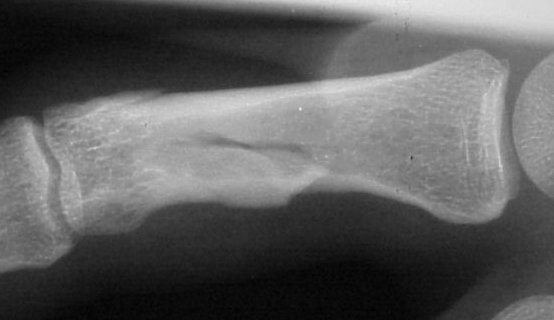

Xrays show a complex intraarticular fracture of the proximal phalanx head. There is a displaced spiral oblique longitudinal fracture with a second oblique coronal split through the articular surface of the radial condyle.

Palmar displacement of a portion of one condyle is visible on the lateral view.